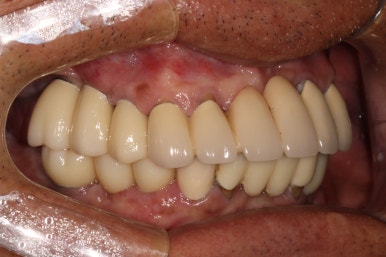

최종보철물을 연결해드리는 오늘,

환자분의 환한 미소가 빛을 발하는 순간입니다.

모든 최종 보철물을 연결하고 나서 치과용 파노라마 사진입니다.

정말 깔끔하게 제작된 것을 보시 수 있을겁니다.

'미적 기준'은 보편적인 측면이 있습니다. 뭔가 나란하고 비율이 대칭인 임플란트는, 잘 모르는 사람이 봐도 잘 되었구나~~ 라고 생각하게 만들어주죠 ^^

정면 사진입니다! 사실 앞니는 가지고 계신 그대로 사용하고 있어 큰 변화가 없어 보입니다만..

상당히 가지런히 구성지게 어금니를 만들어드린 것을 보실 수 있을거에요!